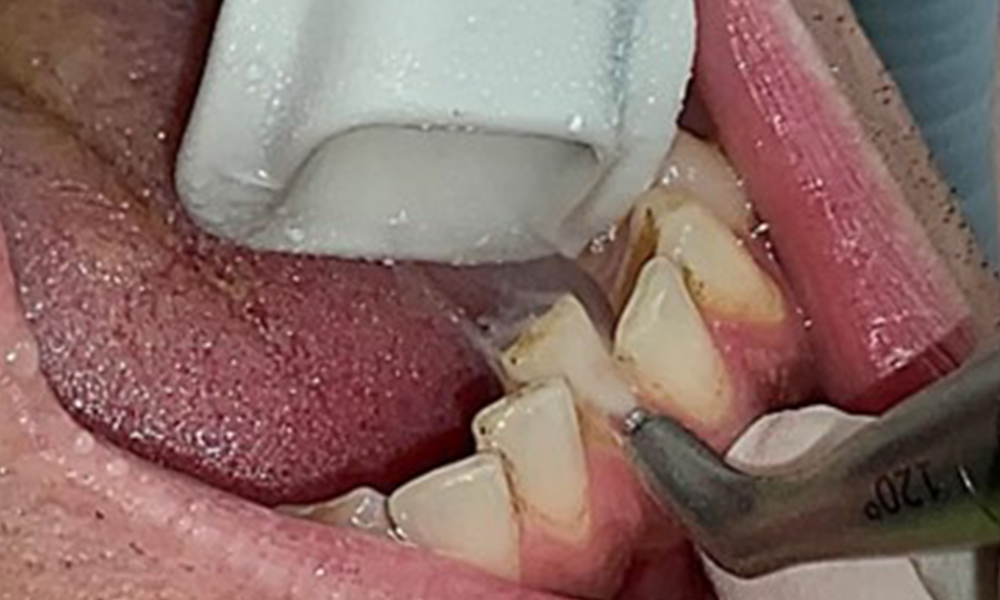

Целта е да се контролира рискът от заболяване чрез отстраняване на супрагингивалния и субгингивалния биофилм. Инструментите трябва да бъдат подбрани въз основа на нуждите на пациента. Първо трябва да се отстранят зъбният камък и всички конкременти с помощта на ултразвукови и/или ръчни инструменти (фиг. 10).